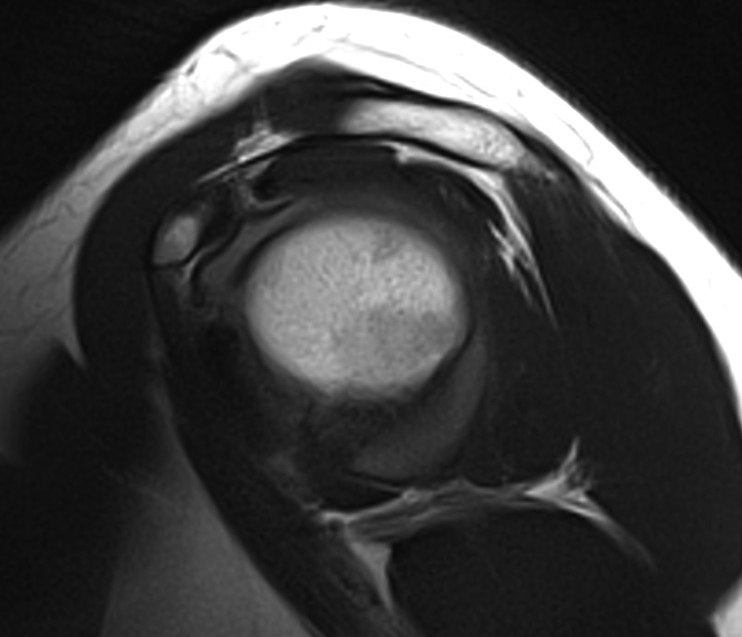

MRI

Mass lesions

Atrophy of T minor

Assess RC